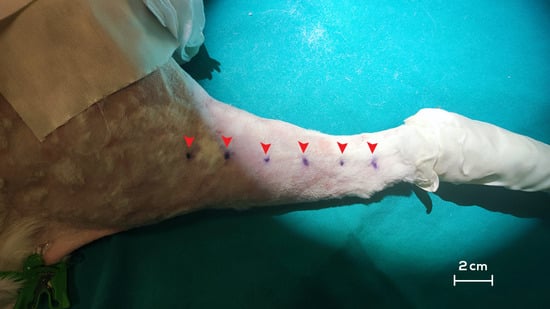

2.2. Intra-Operative Procedures

- Campos, J.L.; Pons, G.; Rodriguez, E.; Al-Sakkaf, A.M.; Vela, F.J.; Pires, L.; Jara, M.J.; Sánchez-Margallo, F.M.; Abellán, E.; Masiá, J. Popliteal vascular lymph node resection in the rabbit hindlimb for secondary lymphedema induction. J. Vis. Exp. 2022, 189, e64576. [Google Scholar] [CrossRef]